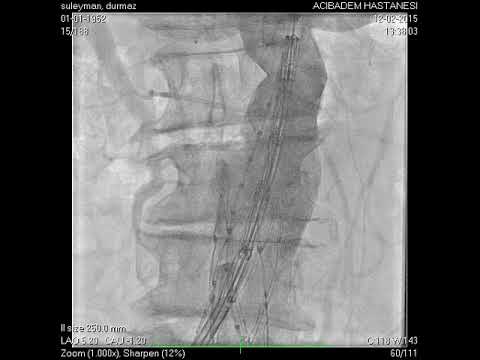

Anjiyografik İşlemler

Kapat